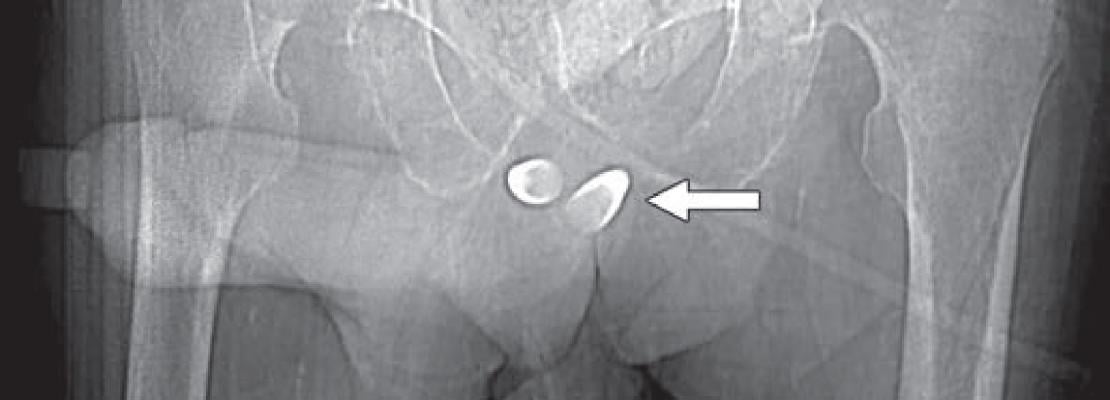

Scout image from contrast-enhanced CT shows erectile implant; stainless steel and silicone anchors (arrow) transfixed to pubic bone are asymmetric.

When evaluating urethral complications from phalloplasty in trans-males, because the neo-to-native urethra anastomosis site will evidence diameter differences, retrograde urethrograms can result in stricture overdiagnosis. Apropos, preliminary assessments should be for functional stricture, alongside the performance of urodynamic studies. “However,” noted Doo, “for confirmation of stricture with abnormal function tests and also for evaluation for fistula, a retrograde urethrogram or voiding cystourethrogram can be obtained.” Should a patient desire erectile potential with the fully-healed neophallus, an implant may be placed, which is prone to infection, attrition, malposition and constituent separation (Fig. 2).

Fig. 2 — Scout image from contrast-enhanced CT shows erectile implant; stainless steel and silicone anchors (arrow) transfixed to pubic bone are asymmetric.